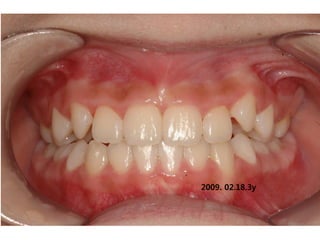

2009. 02.18.3y

2009.08.11 3y6m

2010.06.15 4y4m

2012 02 01

out of Tr 2yr